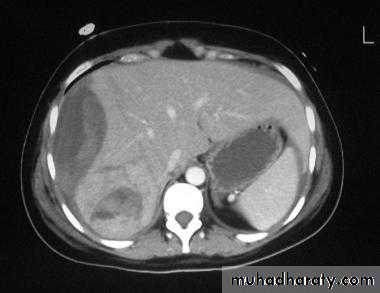

• Contrast-enhanced CT is the investigation of choice for suspected abdominal injuries in hemodynamically stable patients.

Signs of abdominal trauma that may be seen on CT:

• Free blood: hypodense material in more dependent parts of the peritoneal cavity, i.e. pelvis, hepatorenal pouch and paracolic gutters.• Solid organ injury: laceration, fracture, hematoma and contusion

• Lacerations involving the renal collecting system result in urine leak and urinoma

• Non-functioning kidney due to massive parenchymal damage, vascular pedicle injury or obstructed collecting system due to blood clot.